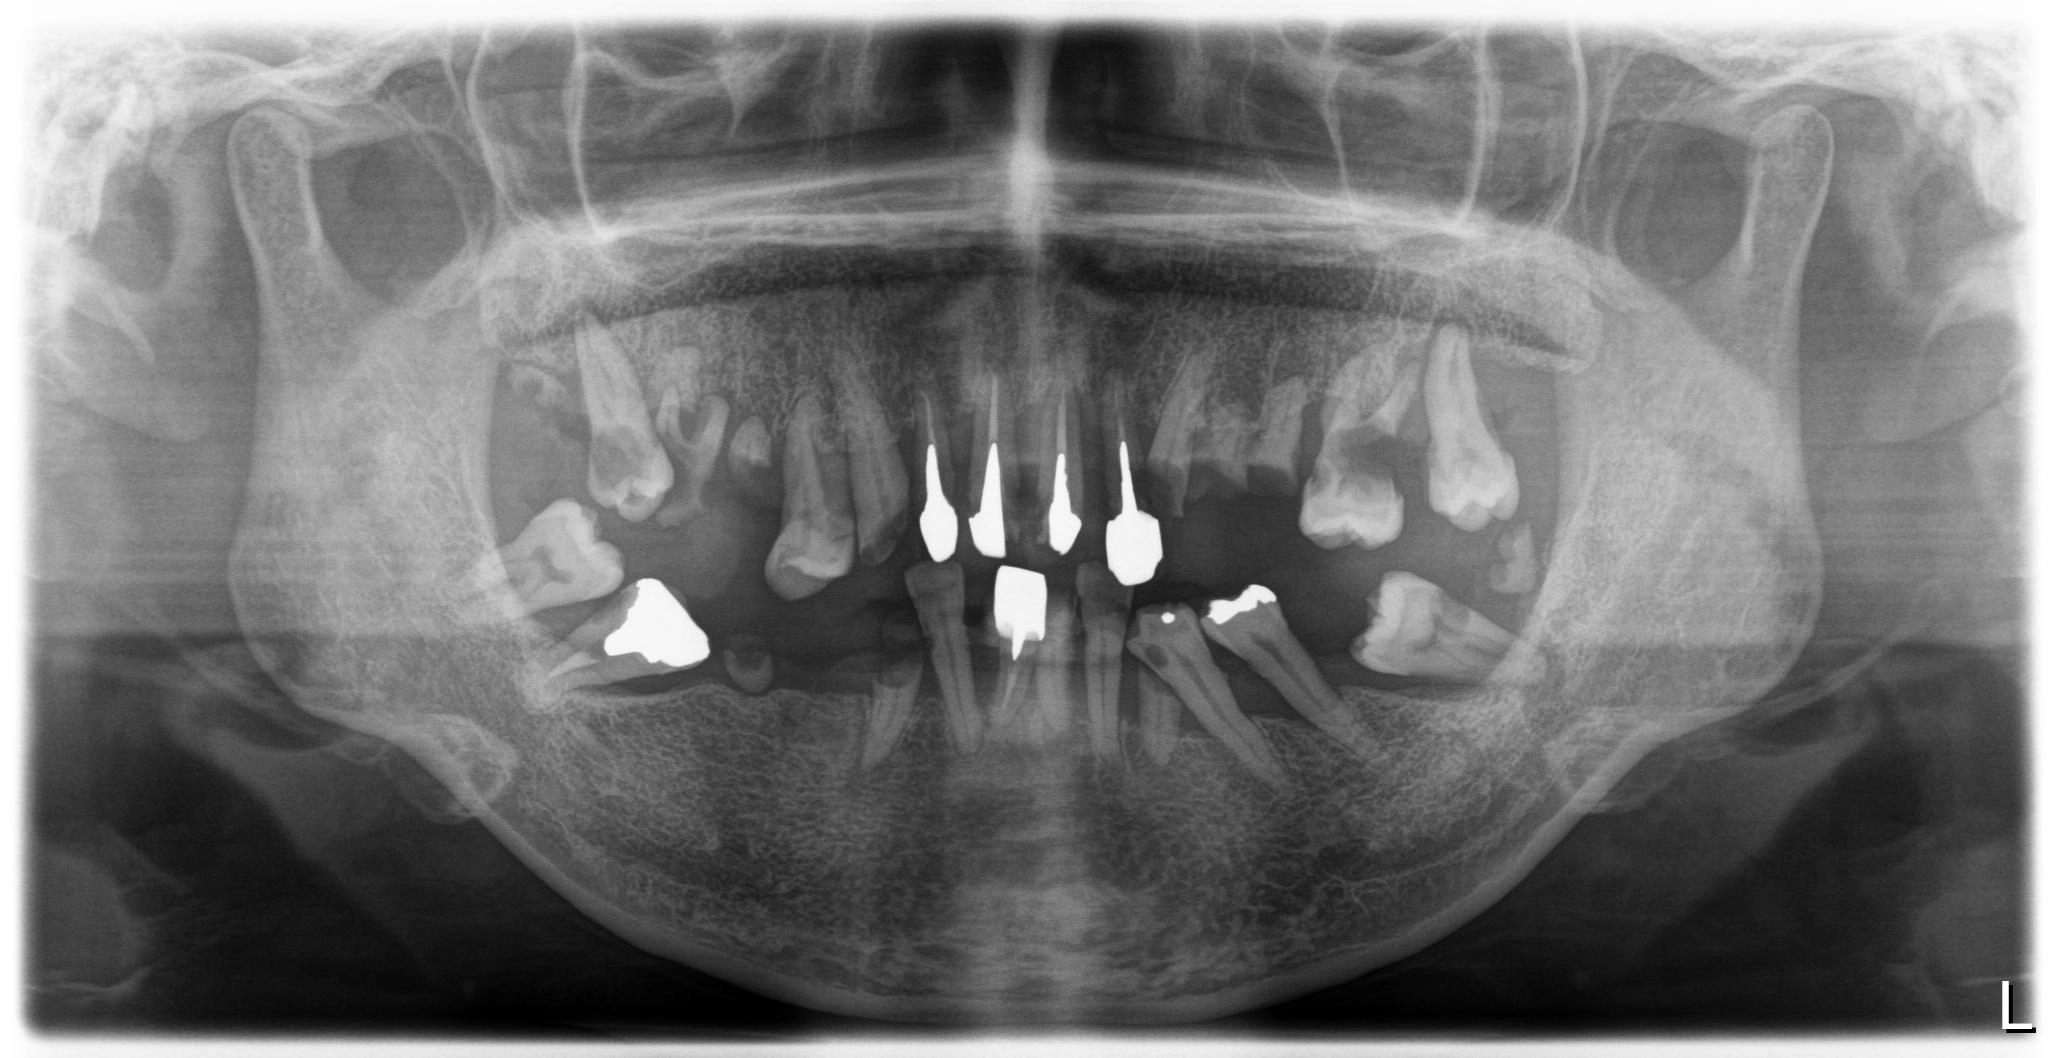

大分県 45歳(女性)

術前

術後

内容 :上下顎オールオン4ザイゴマ0

費用 :4,365,900円

※モニター価格

期間 :半年

リスク:出血・腫れ・痺れ・痛み